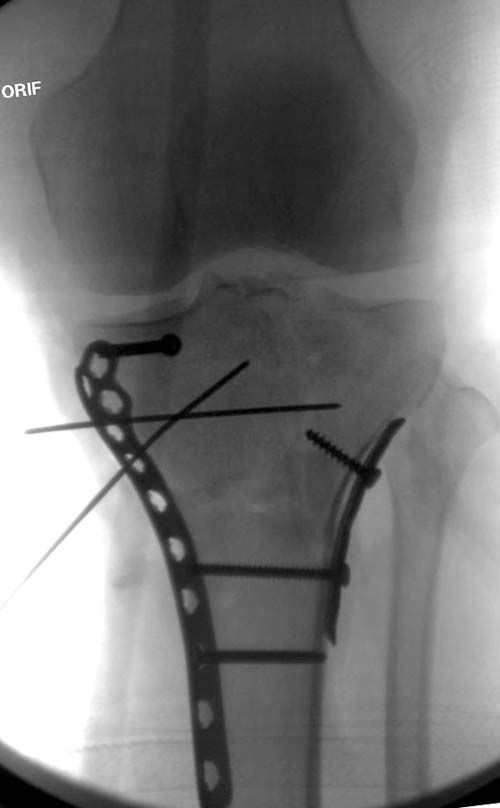

Вытяжение или наружный фиксатор “бедро-голень в виде дельты”. Фиксатор дает свободу, и если условия позволяют, можно отпускать домой. Но главное - надо ожидать проявления “wrinkle sign”! После дистракции можно делать КТ исследование, иначе нестабильные фрагменты искажают данные. Доступ делается по топографии расположения фрагментов, а 3Д картина лучше покажет расположение смещенных мыщелков.

На боковом рентгене, явный задний смещенный компонент. КТ поможет увидеть "вершину" перелома, куда надо поставить антискользящую пластину из заднего или задне-медиальнего доступа. Для стабилизации боковой колонны традиционный боковой доступ через Girdle tubercle с длинной блокирующей пластиной. Одна задняя подпорка не удержит медиальную колонну, требуется длинная медиальная пластина.

Перелом сложный, и для окончательного успеха потребуется арсенал фиксаторов и наличие опыта разных доступов. К успеху приведет только тщательное планирование. Возможно, фиксировать не удастся все за раз. Если во время операции возникнет опасность развития отека в ране, “damage control” операцию надо отложить, лучше поэтапно, чем осложнение.

.Здесь примеры...